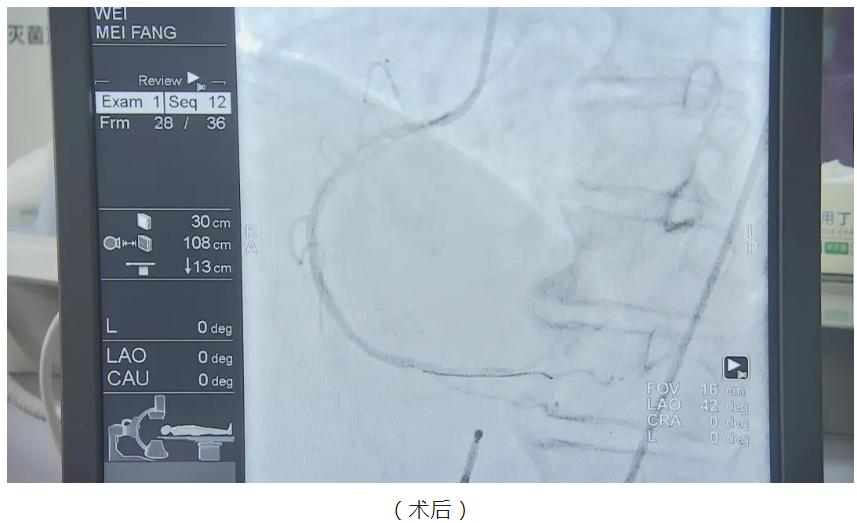

当时,卫阿姨是由家属驱车自行前往就近的奉城医院救治,刚到急诊科门口,卫阿姨就突然晕倒,心脏、呼吸骤停,情况十分危急。据董医生回忆:“当时她这个情况是血压低,我们称为心源性休克,心梗合并心源性休克死亡风险在80%左右,非常不巧的是,这位患者又出现了室性心律失常风暴(俗称电风暴),死亡率更是高达九成以上,所以像这样的病人,一定要抢救及时,这个患者我们反复除颤了20次,如果晚到5分钟,肯定是救不过来了。”

实际上,在奉城医院,像这类急性心肌梗死合并电风暴抢救成功也并非偶然。自奉城医院成立奉贤区冠心病临床诊疗中心后,作为奉贤东部的区域性医疗中心,近年来,奉城医院的冠心病介入诊疗已逐渐达到了精准介入的治疗水平,期间开展冠心病介入诊疗病例近900例,挽救了大量急性心肌梗死患者的生命,也获得了地区冠心病患者的认可。